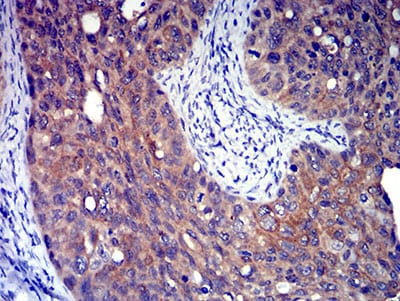

分类: 科研抗体货号: 31308别名: P2Y8应用: IHC,IF,FCM反应种属: Human

分类: 科研抗体货号: 31307别名: P2Y8应用: IHC,IF,FCM反应种属: Human